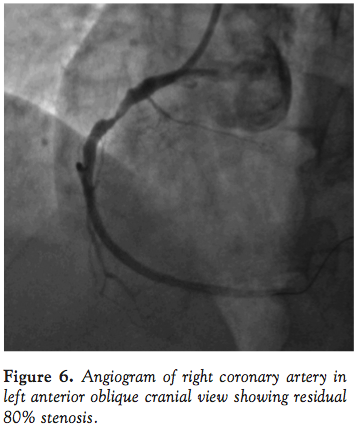

negative suction, the guide catheter was slowly withdrawn from the artery and out of the femoral sheath. Flushing of the guide catheter revealed chunks of intact thrombus that matched the filling defect (Figure 4). While all this was done, the stabilizer wire was in the RCA to ensure access to the distal RCA. There was significant improvement in blood pressure of the patient along with relief in the chest pain. A 7 Fr guide catheter was passed over the stabilizer wire and the RCA was engaged (Figure 5). Angiogram revealed a widely patent artery with TIMI III flow and a residual stenosis of 80% in mid segment of the RCA (Figure 6). The lesion was stented with a non-drug-eluting Prokinetic stent 4 mm x18 mm (Biotronik AG). Post-dilatation, patient developed slow flow, which was successfully managed. Final angiogram showed a well-expanded stent with TIMI III flow (Figure 7). Post-procedure hospital course of the patient was uncomplicated and he was discharged on dual antiplatelet regimen on day 4.